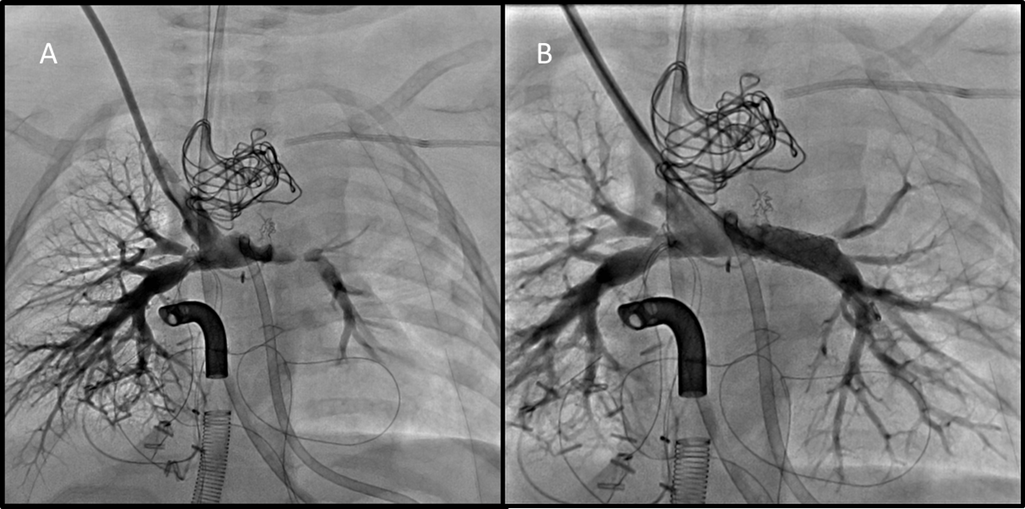

After removal of the MVP either transcatheter or at time of surgical intervention, it is possible that there will be stenosis and deformation of the branch PA anatomy (Figure 4) requiring catheter intervention and stenting.

Figure 4

Figure 4. Angiographic evaluation of pulmonary arteries following comprehensive stage II palliation and surgical removal of PFRs. A. Angiogram in SVC demonstrates mild proximal RPA distortion, and moderate to severe LPA stenosis. B. Angiogram performed following 7mm stent placement in LPA showing significant angiographic improvement.